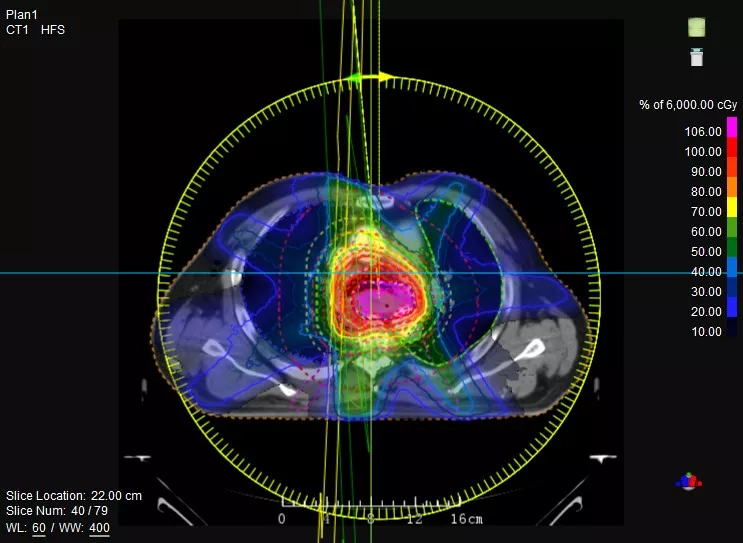

機(jī)載CT影像可直接用于放療計(jì)劃制作

CT-IGRT配準(zhǔn),除骨性標(biāo)記外,還能以器官、軟組織等作為參考,真正找到配準(zhǔn)目標(biāo)

鼻咽癌患者,進(jìn)行旋轉(zhuǎn)容積調(diào)強(qiáng)治療(uARC)

一體化CT-linac讓自適應(yīng)放療ART概念變?yōu)楝F(xiàn)實(shí)?;颊呷煶虪顟B(tài)監(jiān)控,適時(shí)在線調(diào)整治療計(jì)劃,精準(zhǔn)控制治療劑量,為患者動(dòng)態(tài)定制個(gè)體化治療方案。uAI賦能智能勾畫(huà)和自動(dòng)計(jì)劃,秒級(jí)勾勒靶區(qū)和危及器官,大幅縮短自適應(yīng)放療時(shí)間。